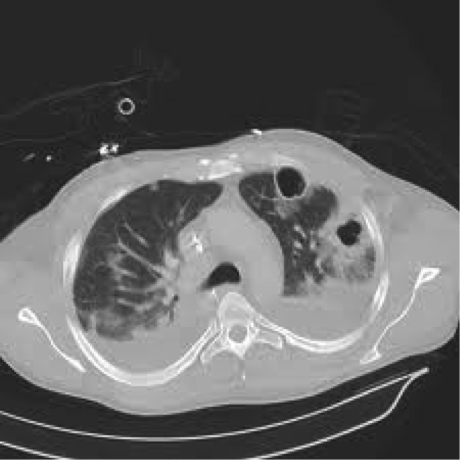

Dz?

Staph aureus pneumonia

(notice two abscesses in left lobe and empyema both sides)